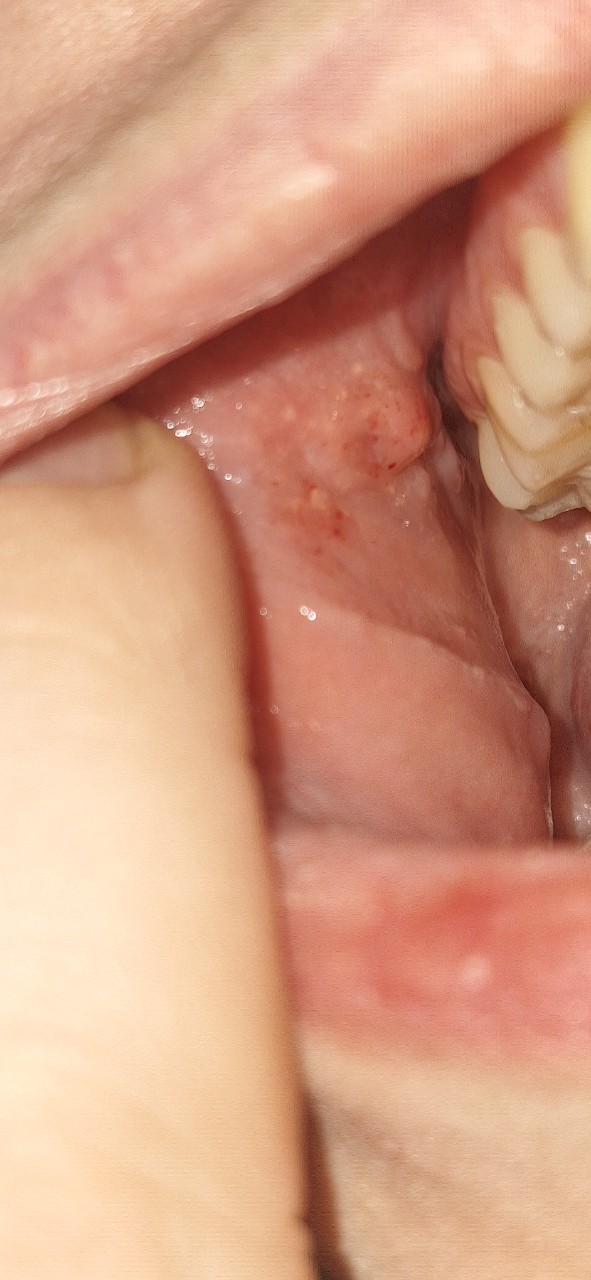

Немного болело горло, заглянула в рот, и справа увидела отекшее и красное на щеке, слева такого нет. Вот я и испугалась. Да, есть привычка, постоянно прикусываю, посасываю и лезу туда языком

На фото обвела, пугает вся эта зона, то что отличается от другой стороны, то что так весит, красная и отекшая.

"Здравствуйте, подскажите пожалуйста, что это может быть на щеке? " - Там много чего есть. Желтые пятнышки — сальные железы, так называемые гранулы Фордайса. Есть красные точки — предположительно, из-за вредной привычки подсасывать щеку к зубам. По этой же причине можно увидеть так называемую "белую линию щеки".

Да, забыл добавить, там еще свисает, как сосочек — это место на слизистой щеки, где открывается устье выводного протока околоушной слюнной железы.